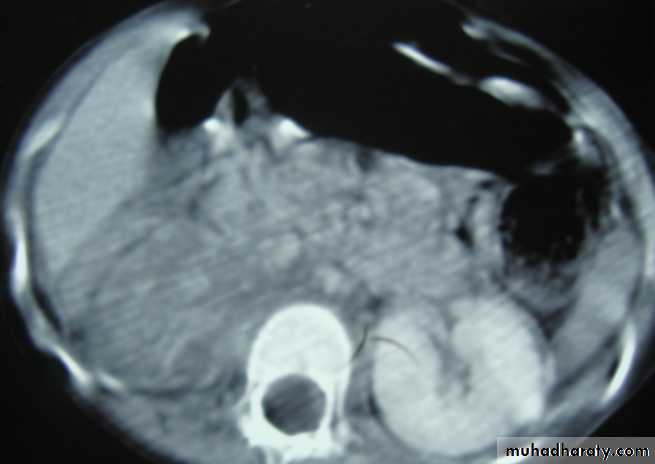

Crescent sign of perinephric abscess complicated from a pyelonephritis

Percutaneous drainage by wide bore for the thick pusWhat's management?